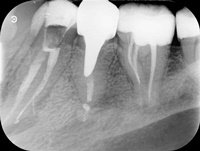

Pacjentka zgłosiła się z bólem. Ząb prawa dolna czwórka po leczeniu kanałowym. Nawracające dolegliwości bólowe, od kilku lat okresowo zaostrzające się. Podjęto decyzję o rewizji leczenia kanałowego. Udróżniono kanał korzeniowy, oraz odnaleziono kanał dodatkowy. Zdjęcie początkowe i zdjęcie po leczeniu endodontycznym pod mikroskopem.